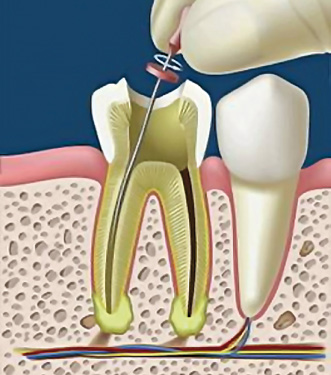

L'Endodonzia è quella branca dell'odontoiatria che si occupa delle terapie dell'endodonto, ovvero la parte interna del dente, che contiene la polpa dentale. Il dente infatti non è interamente formato dalla dentina e dallo smalto, ma custodisce al suo interno degli elementi connettivi e nervosi, che formano appunto la polpa dentale. La corona, la parte più esterna del dente, quella che si erge dalle gengive, contiene la camera pulpare, dalla quale partono dei canali radicolari che raggiungono l'apice della radice.

Il numero di canali e radici non è sempre uguale, e cambia da dente a dente. In linea di massima si può dire che i denti anteriori hanno un solo canale e una sola radice, nei premolari è possibile trovare due canali per altrettante radici, mentre nei molari si arrivano ad avere tre radici e a volte anche quattro canali.

L'importanza di una cura canalare eseguita secondo determinati protocolli risulta importante per evitare eventuali problemi futuri al paziente. Il trattamento di un dente varia da 2 a più sedute, dipende dal numero di radici da trattare. Durante il trattamento di Devitalizzazione e a fine terapia vengono fatte sempre delle radiografie di controllo per valutare l'effettiva riuscita della cura.